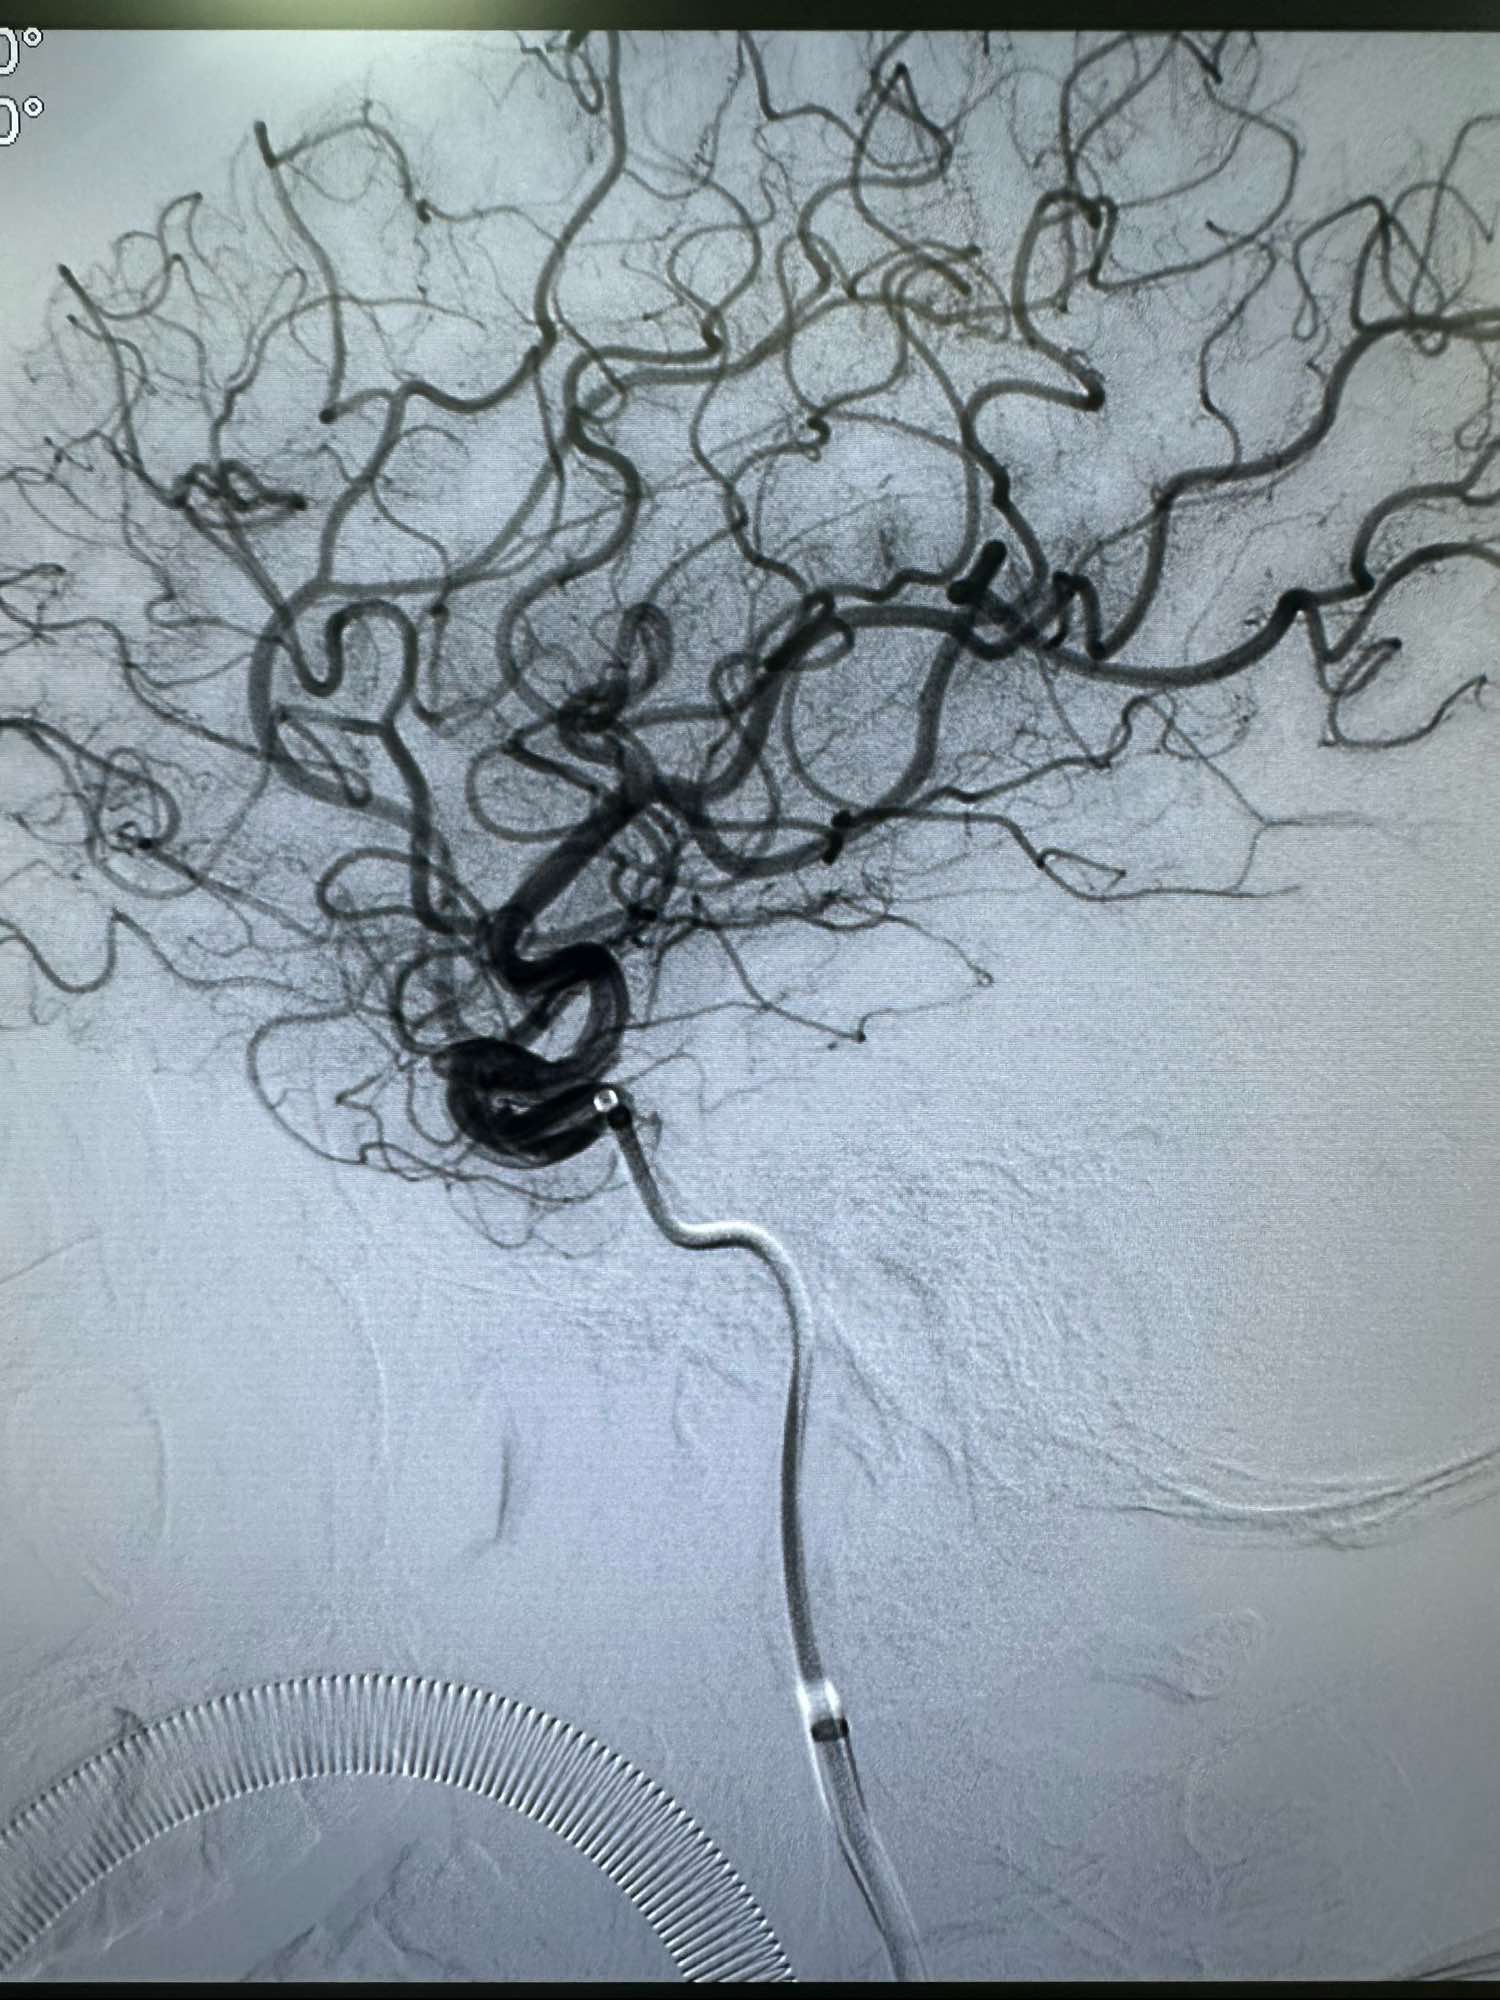

侧位